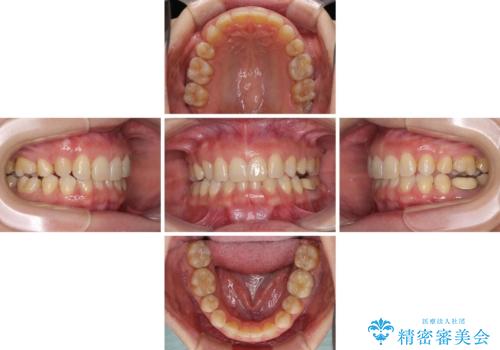

マウスピースでの抜歯矯正特有の抜歯スペースに向かって奥歯が傾斜する動きが顕著に表れ、ディープバイトは改善されませんでした。

前歯のみが強く接触し、奥歯で咬めない期間も続いたため、ワイヤー装置などを補助的に使用し、何とか終了させることができました。